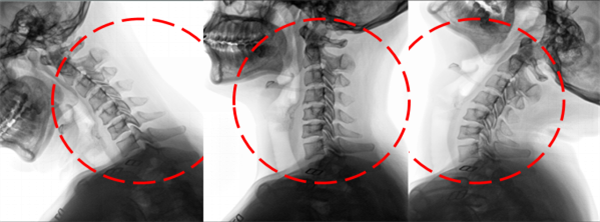

与此同时,立位锥束容积成像f-DR在运动功能成像领域也展现出了卓越的性能。通过先进的AI图像处理算法,它能够精准提取患者关节、脊柱的运动轨迹,并对其进行深入分析。这一过程,如同为患者的运动系统绘制了一幅详尽的“运动地图”,使得医生能够更准确地评估腕关节骨折、椎体滑脱等疾病的康复状态。